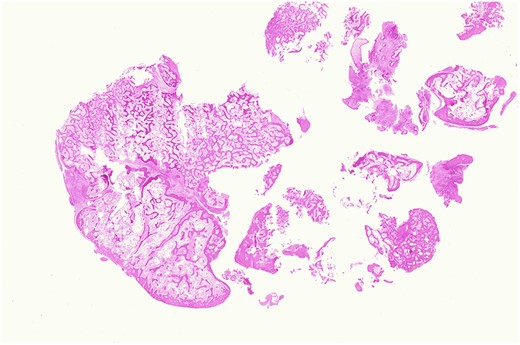

Both specimens showed identical histopathological features, being composed of chronically inflamed nasal mucosa undermined and compressed by sharply demarcated, zonated, multilobulated osseous proliferation without any cartilaginous component. The core and bulk of the lesions was composed of anastomosing, cancellous type bony trabeculae separated by fibrofatty marrow spaces, surfaced by denser cortical type bone, features characteristic of benign osteoma (Figs 2 and 3).

Osteoma, high-magnification photomicrograph. Scanning power photomicrograph showing disrupted pieces of multilobulated variably hyperostotic bone characterized by central anastomosing cancellous trabeculae and fibro-adipocytic interstices, surmounted by more sclerotic cortical type bone. Note the complete absence of any chondroid element (H&E stain, original magnification ×1).